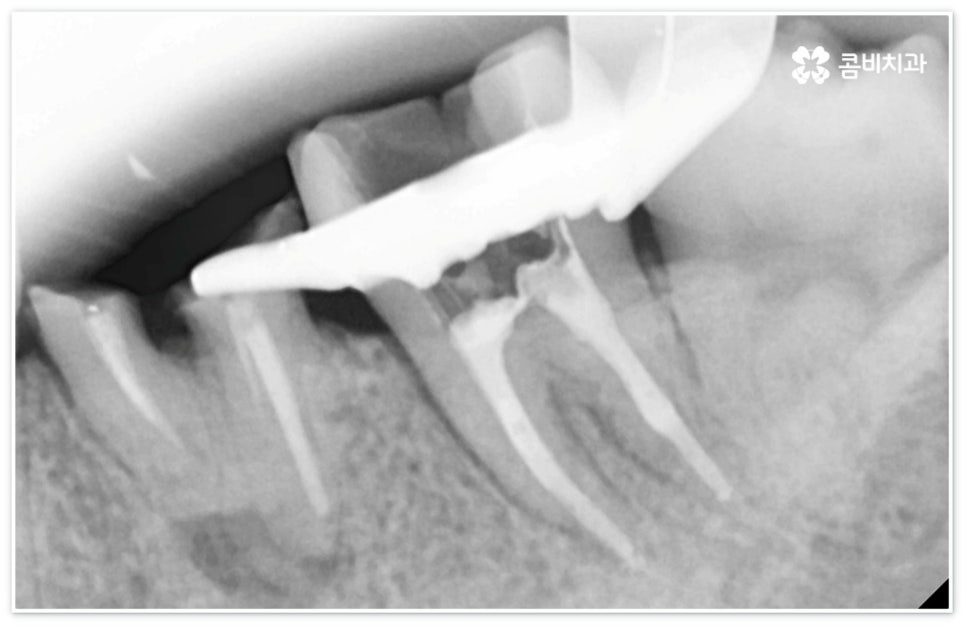

신경치료는 일견 간단해 보일 수 있으나 사람의 신경이 매우 얇고 또한 환자분들마다 신경관의 개수와 모양이 다 다르기 때문에 오염된 부위를 끝까지 깨끗하게 제거하기 위해서는 매우 섬세하고 뛰어난 기술력을 요하므로 다양한 임상 경험을 통해 풍부한 노하우를 가지고 있는 의료진과 함께 하실 필요가 있습니다.

신경치료는 오염된 치수 조직을 제거하여 감염이 더이상 진행되지 않도록 하고 치과용 충전재로 내부를 빈틈없이 채운 후 크라운 보철물을 씌워 남아있는 자연 치아를 쓸 수 있도록 하는 치료이기 때문에 그 과정에서 치아 깊숙한 곳까지 기구로 파고들어 가므로 주변 치아 조직이 예민해지면서 치료 후 며칠에서 길게는 몇 주까지 신경치료통증 을 느끼실 수 있는데요.

신경치료는 자연 치아를 보존할 수 있는 거의 마지막 단계의 치료라고 할 수 있으므로 만약 이 시기도 놓쳐서 신경치료를 할 수 없을 정도로 치아에 손상이 심각하다면 발치 후 임플란트 식립을 진행해야 할 거예요. 현대에 임플란트 관련 기술이 많이 발달하여 보다 편안한 사용이 가능해졌다고 하지만 자신이 타고난 치아를 따라갈 수는 없을 것이기 때문에 될 수 있는대로 자연 치아의 수명을 늘리는 방향으로 보존 치료를 해 줄 필요가 있는데요. 그러나 구강 질환이나 사고 등을 이유로 신경치료 등으로도 살릴 수 없이 이미 수명을 다한 치아의 경우 기능적으로나 심미적으로나 빠르게 대체해 주어야 할 거예요.